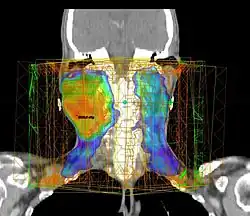

Przykładowy układ wiązek promieniowania w radioterapii guza mózgu

Przekrój z badania (tomografi komputerowej) CT z dawką promieniowania, przykładowy układ wiązek promieniowania w radioterapii nowotworu głowy i szyi, technika radioterapii IMRT

Przekrój ciała Pacjenta z rozkładem dawki promieniowania z nowotworem Głowy i Szyi leczonego techniką IMRT. Kolor pomarańczowo-zielony wyższa dawka, kolor niebieski niższa dawka